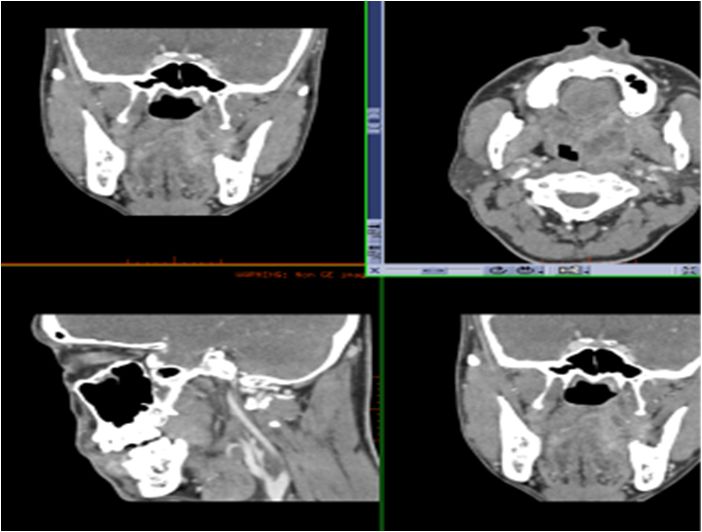

01 眶下间隙

女,31岁,前牙区肿胀不适。

牙根尖周骨质破坏,唇侧皮质不连续,周围软组织肿胀,提示眶下间隙感染。